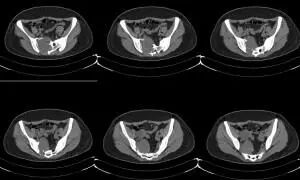

额外的成像模式通常有助于恶性软骨损伤的诊断和分期。 计算机断层扫描(CT)可以评估骨质构造的内皮层剖分,皮层增厚或破裂。 此外,CT有助于确定钙化的模式和程度。